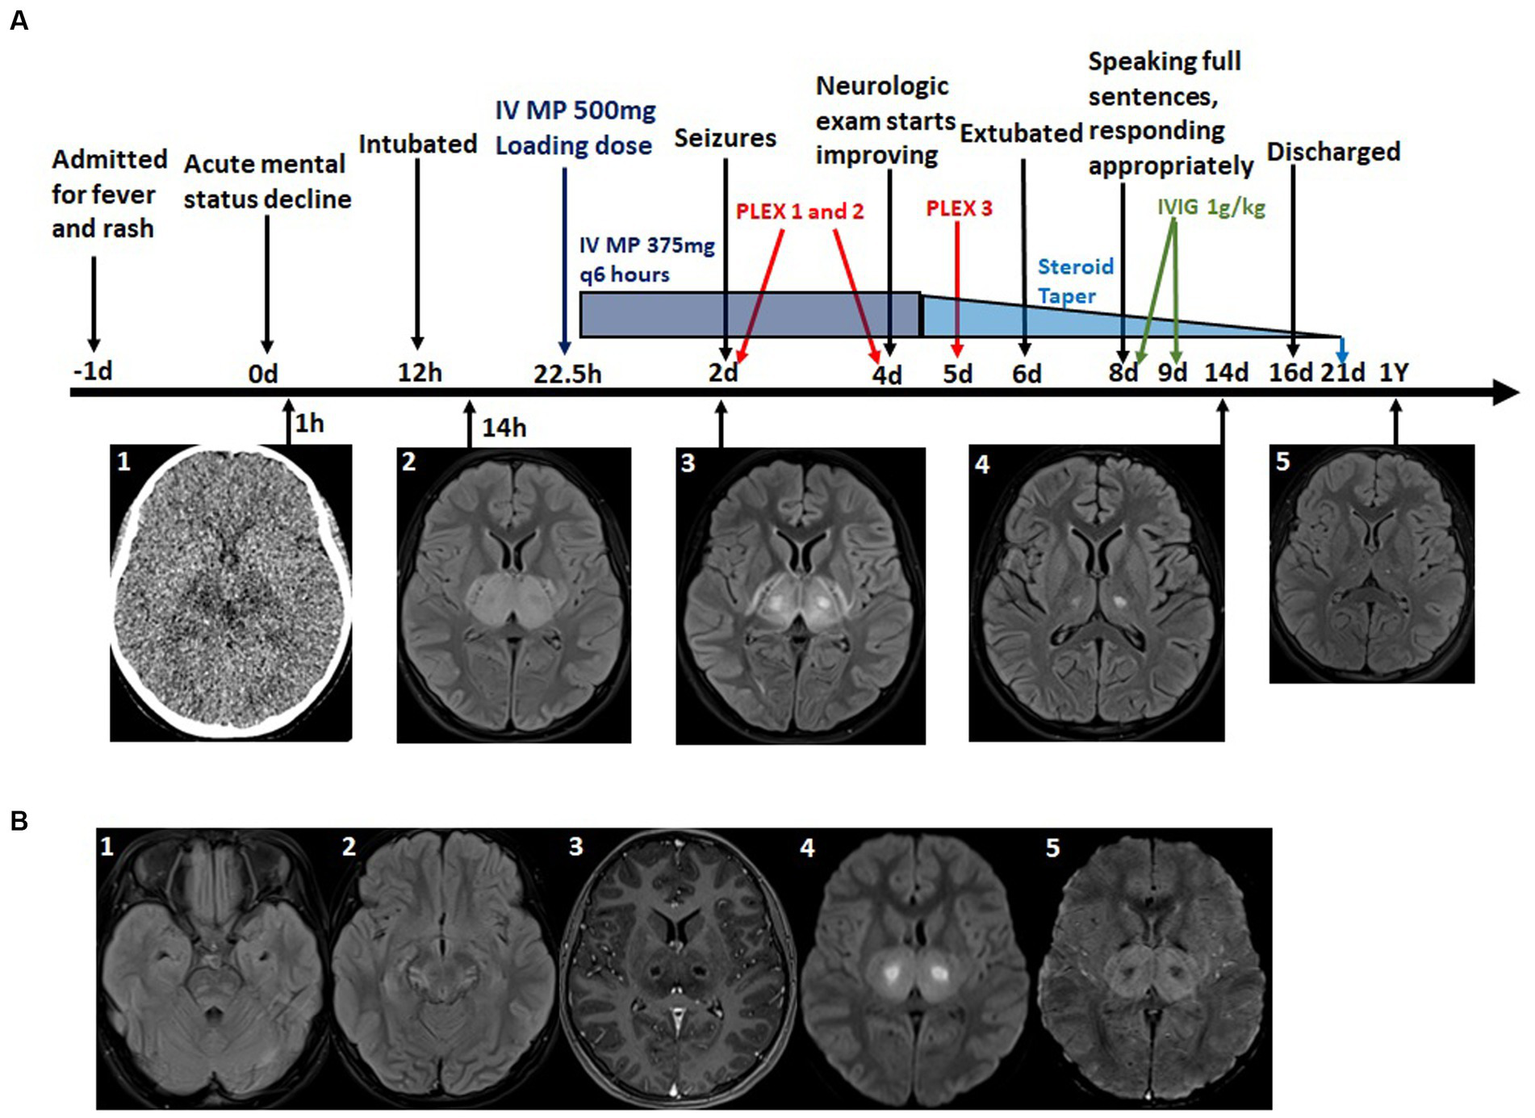

A 10-year-old previously healthy female first presented to an outside hospital with fever, malaise, and abdominal pain. It was presumed to be due to a urinary tract infection and she was discharged home on amoxicillin. Two days later, she returned to the same emergency department for persistent fevers. Labs revealed neutropenia, elevated transaminases, elevated D-dimer and lactate dehydrogenase and viral testing, including COVID-19, was negative (Table 2). She was again discharged with a longer course of different antibiotics. While at home she continued to be febrile and developed worsening abdominal pain and new diarrhea. Several days later, now 3 weeks from the onset of her symptoms, she developed higher fevers and a new rash, which prompted return to the emergency department. At that time, her exam was notable for hepatomegaly and a diffuse erythematous blanching macular rash. She had worsening leukopenia but down-trending transaminases (Table 2). She was admitted to the acute care floor where cultures were obtained, and IV antibiotics were initiated. It is noteworthy that, while she had a multitude of other systemic symptoms, her mental status remained intact until the first night of admission, per report of her parents. On the night of admission, she acutely developed diplopia, hallucinations, and progressive lethargy over several hours with head computed tomography (CT) demonstrating symmetric hypodensities in the bilateral thalami (Figure 2).

Figure 2

(A) Timeline of major clinical events, Imaging findings and immunosuppressive treatments. A1: CT scon at time of mental status change-bilateral thalamic hypodensities. A2–5: T2 Flair MRI at level of thalamus at indicated time points-time course of resolution of bilateral thalamic lesions. (B) Additional relevant MRI imaging findings. B1: T2 Flair MRI at time of initial MRI-bilateral pontine hyperintensity, subtle right temporal lobe edema. B2: T2 Flair MRI on day 2 - midbrain edema. B3: T1 with contrast MRI demonstrating ring enhancing thalamic lesions. B4: Diffusion weighted imaging (DWI) MRI-core of thalamic lesions restrict diffusion. B5: Susceptibility weighted imaging (SWI) MRI hemorrhage in thalamic lesions.

She was transferred to the pediatric intensive care unit (PICU) where she was noted to be confused, agitated, unable to follow commands, and had bowel and bladder incontinence. Her mental status waxed and waned; at worst, she was unresponsive. Hyperreflexia in the bilateral upper and lower extremities were appreciated on exam. Given her mental status, she was endotracheally intubated for airway protection. Antimicrobials were broadened for meningitis and encephalitis coverage. MRI brain, with and without contrast, showed symmetric, bi-thalamic T2 hyperintensity with central oval shaped cystic areas with rim-enhancement, faint hemorrhage, circumferential diffusion restriction, and multifocal T2 hyperintense lesions, consistent with vasogenic edema, in the bilateral cortex, juxtacortical white matter, bilateral hippocampi, midbrain, pons and cerebellum (Figure 2). MRI of the cervical, thoracic, and lumbar spinal cord was not performed at time of the initial diagnosis; however, it was performed prior to discharge and no abnormalities were identified. A diagnosis of ANE was made based on characteristic MRI findings and clinical presentation. An extensive workup for alternative or additional etiologies was completed and ultimately negative (Table 2). Lumbar puncture revealed a cerebrospinal fluid (CSF) protein of 105 (normal <60) (Table 2). Many additional tests were performed and are detailed in Table 2. These tests included genetic testing for RANBP2, and Aquaporin-4 antibodies were both negative. Unfortunately, oligoclonal bands and myelin oligodendrocyte glycoprotein (MOG) antibodies were not sent. Because of fluctuations in level of awareness, she started on continuous electroencephalography (EEG) which showed right sided temporal lobe seizures. She was loaded with fosphenytoin 20 mg/kg resulting in resolution of her seizures. She continued fosphenytoin 100 mg twice per day for maintenance therapy which was transitioned to oral levetiracetam 500 mg twice per day after 10 days. ANE-SS was calculated as 6/9 due to older age, low platelet count, presence of elevated csf protein and presence of brainstem involvement on imaging (Table 3).

She was given a loading dose of IV MP 500 mg 22.5 h after acute mental status decline (Figure 2) and continued IV MP 375 mg every 6 h (total daily dose 30 mg/kg) for four more days. Followed by a 14-day oral steroid taper with prednisone. She received three rounds of PLEX, 1.5 times volume, on days 2, 4, and 5 (originally planned for five rounds, but stopped early due to coagulopathy). Finally, she was given IVIG, 1 g/kg, on days 8 and 9. Because of the association of ANE with impaired cellular metabolism, she was also given a mitochondrial cocktail of nutritional supplements consisting of—CoQ10 2–8 mg/kg/day, Riboflavin 100 mg per day, L-carnitine 100 mg/kg/day, Leucovorin 0.5–2.5 mg/kg per day, Thiamine 100 mg per day, and Biotin 5–10 mg per day. Additional neuroprotective strategies were employed throughout her PICU course, including elevating the head of the bed and maintaining normal oxygenation, normocarbia, normothermia, normotension, normoglycemia, and normonatremia.

After 24 h of high dose steroids, her mental status improved with the ability to follow commands. Antimicrobials were discontinued when cultures and infectious studies were negative at 48 h. Four days following PICU admission, she was extubated. Upon transfer to the pediatric floor, she was alert and oriented with fluent speech and no cranial nerve deficits. She had generalized weakness, but was able to ambulate short distances without assistance. Repeat brain MRI 14 days after her initial study demonstrated marked improvement of previously noted edema with minimal residual abnormal T2 signal in the bilateral thalami, inferior and high frontal cortex (Figure 2).